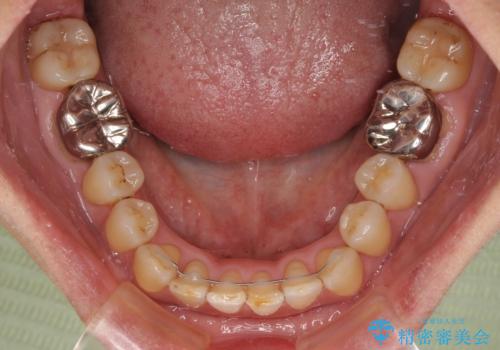

前歯の後戻り インビザラインでの再矯正治療

- かつて抜歯矯正を行ったものの、後戻りをしてしまったとのことで来院された患者様です。

上顎前歯が前突し、隣の歯が裏側に移動してきている状態でした。

飲み込みの状態を確認したところ、舌の突出癖が認められたため、それによる後戻りの可能性が高いと考え、舌のトレーニングを指導しました。

舌のトレーニングをしっかりと行ってくださり、10ヶ月で希望通りの歯列となりました。